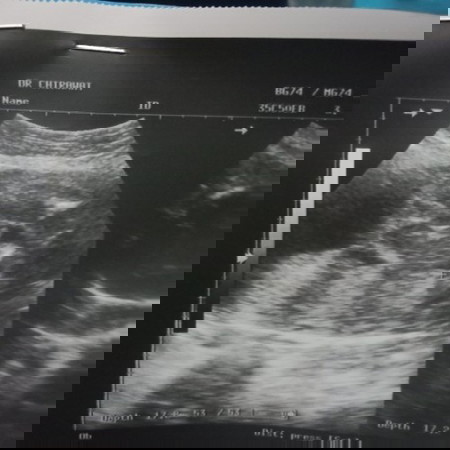

อัลตร้าซาวด์

ขออนุญาตจ้า ช่วยดูให้หน่อยผช.มั้ยค่ะ แม่ซาวด์มา3รอบ รอบนี้หมอบอกผช.จ้า รอบแรกผช. รอบสองผญ. รอบนี้ผช. ซาวด์คนละหมอคนละที่หมดเลยจ้า ขอบคุณค่ะ